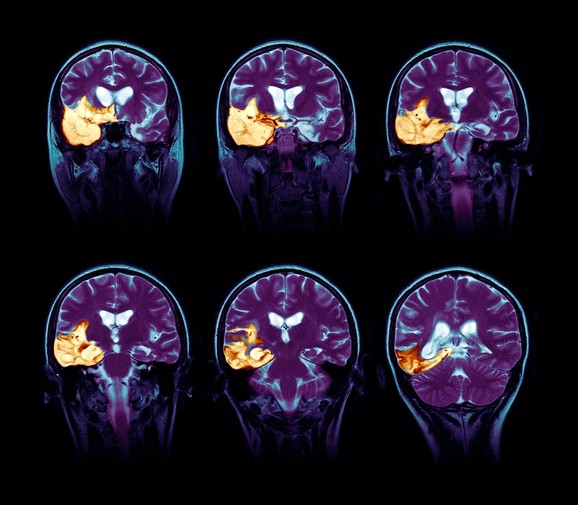

Sajma je smeštena na odeljenje za intenzivnu negu i tokom sledeća 24 sata lekari su izvršili niz testova, koji su otkrili veliki otok na mozgu.

Ali, za taj jedan dan njen mozak je toliko otekao da lekari nisu mogli ni ponovo da ga skeniraju jer je bilo previše riskantno da je pomeraju.

On sada želi da podigne svest o ovom oboljenju, koje godišnje pogodi 6.000 ljudi samo u Velikoj Britaniji, a usmrti oko 1.800. Encefalitis uzrokuje virusna infekcija koja napadne mozak, ili imuni sistem koji greškom napada mozak. Svaki virus ima potencijal da uzrokuje encefalitis, jer može doći do mozga krvotokom. Retko, iako je moguće, do oboljenja će dovesti i bakterije i gljivice, ili ujed krpelja. Međutim, u Sajminom slučaju uzrok nije poznat.